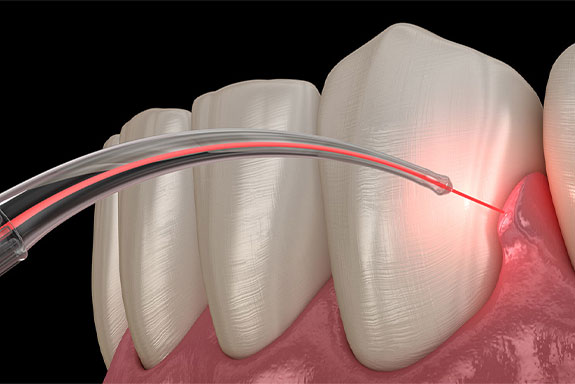

Laser Dentistry

Dental technology has come a long way in recent years, and one of the most exciting developments is the use of lasers in dentistry. Laser dentistry is a minimally invasive approach that offers many benefits over traditional methods. At our practice, we are proud to offer this state-of-the-art technology to our patients.

Dr Deepak Victor addresses anxiety through a compassionate, patient-first approach. Every pain-inducing procedure is administered with local anaesthesia with precision to ensure a completely numbed area beforehand. Modern techniques that are gentle are prioritised to minimise pressure and vibration during procedures. Adoption of advanced tools such as digital scanners and laser technology reduces the need for invasive methods significantly. The whole clinical environment is designed to be relaxing, ensuring peace of mind throughout the visit.